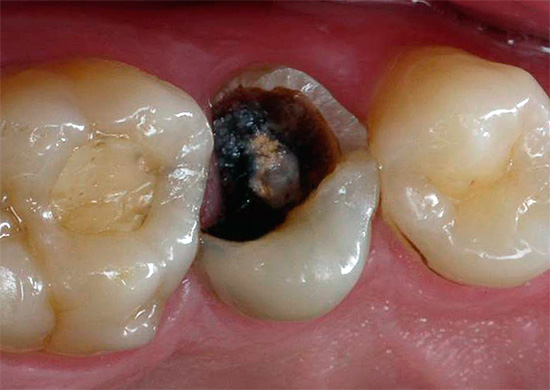

pulpite È una malattia in cui si verifica l'infiammazione del cosiddetto "nervo" dentale (polpa). I molari grandi (molari) hanno spesso tre canali, in ciascuno dei quali è presente un fascio neurovascolare. Quando si verifica un processo infiammatorio nella polpa, si gonfia e si stringe, a seguito del quale una persona può sentire un forte dolore.

La pulite richiede un trattamento obbligatorio: non dovresti aspettarti che tutto si risolva in qualche modo e il dolore scompare da solo, come a volte accade con il dolore con carie. Il dolore può davvero scomparire quando il "nervo" muore completamente, ma poi inizia a decomporsi proprio all'interno del dente e senza un trattamento adeguato non porterà a nulla di buono.

- preparazione di tessuti molli cariati con punta di una turbina, rimozione di dentina necrotica e pigmentata;